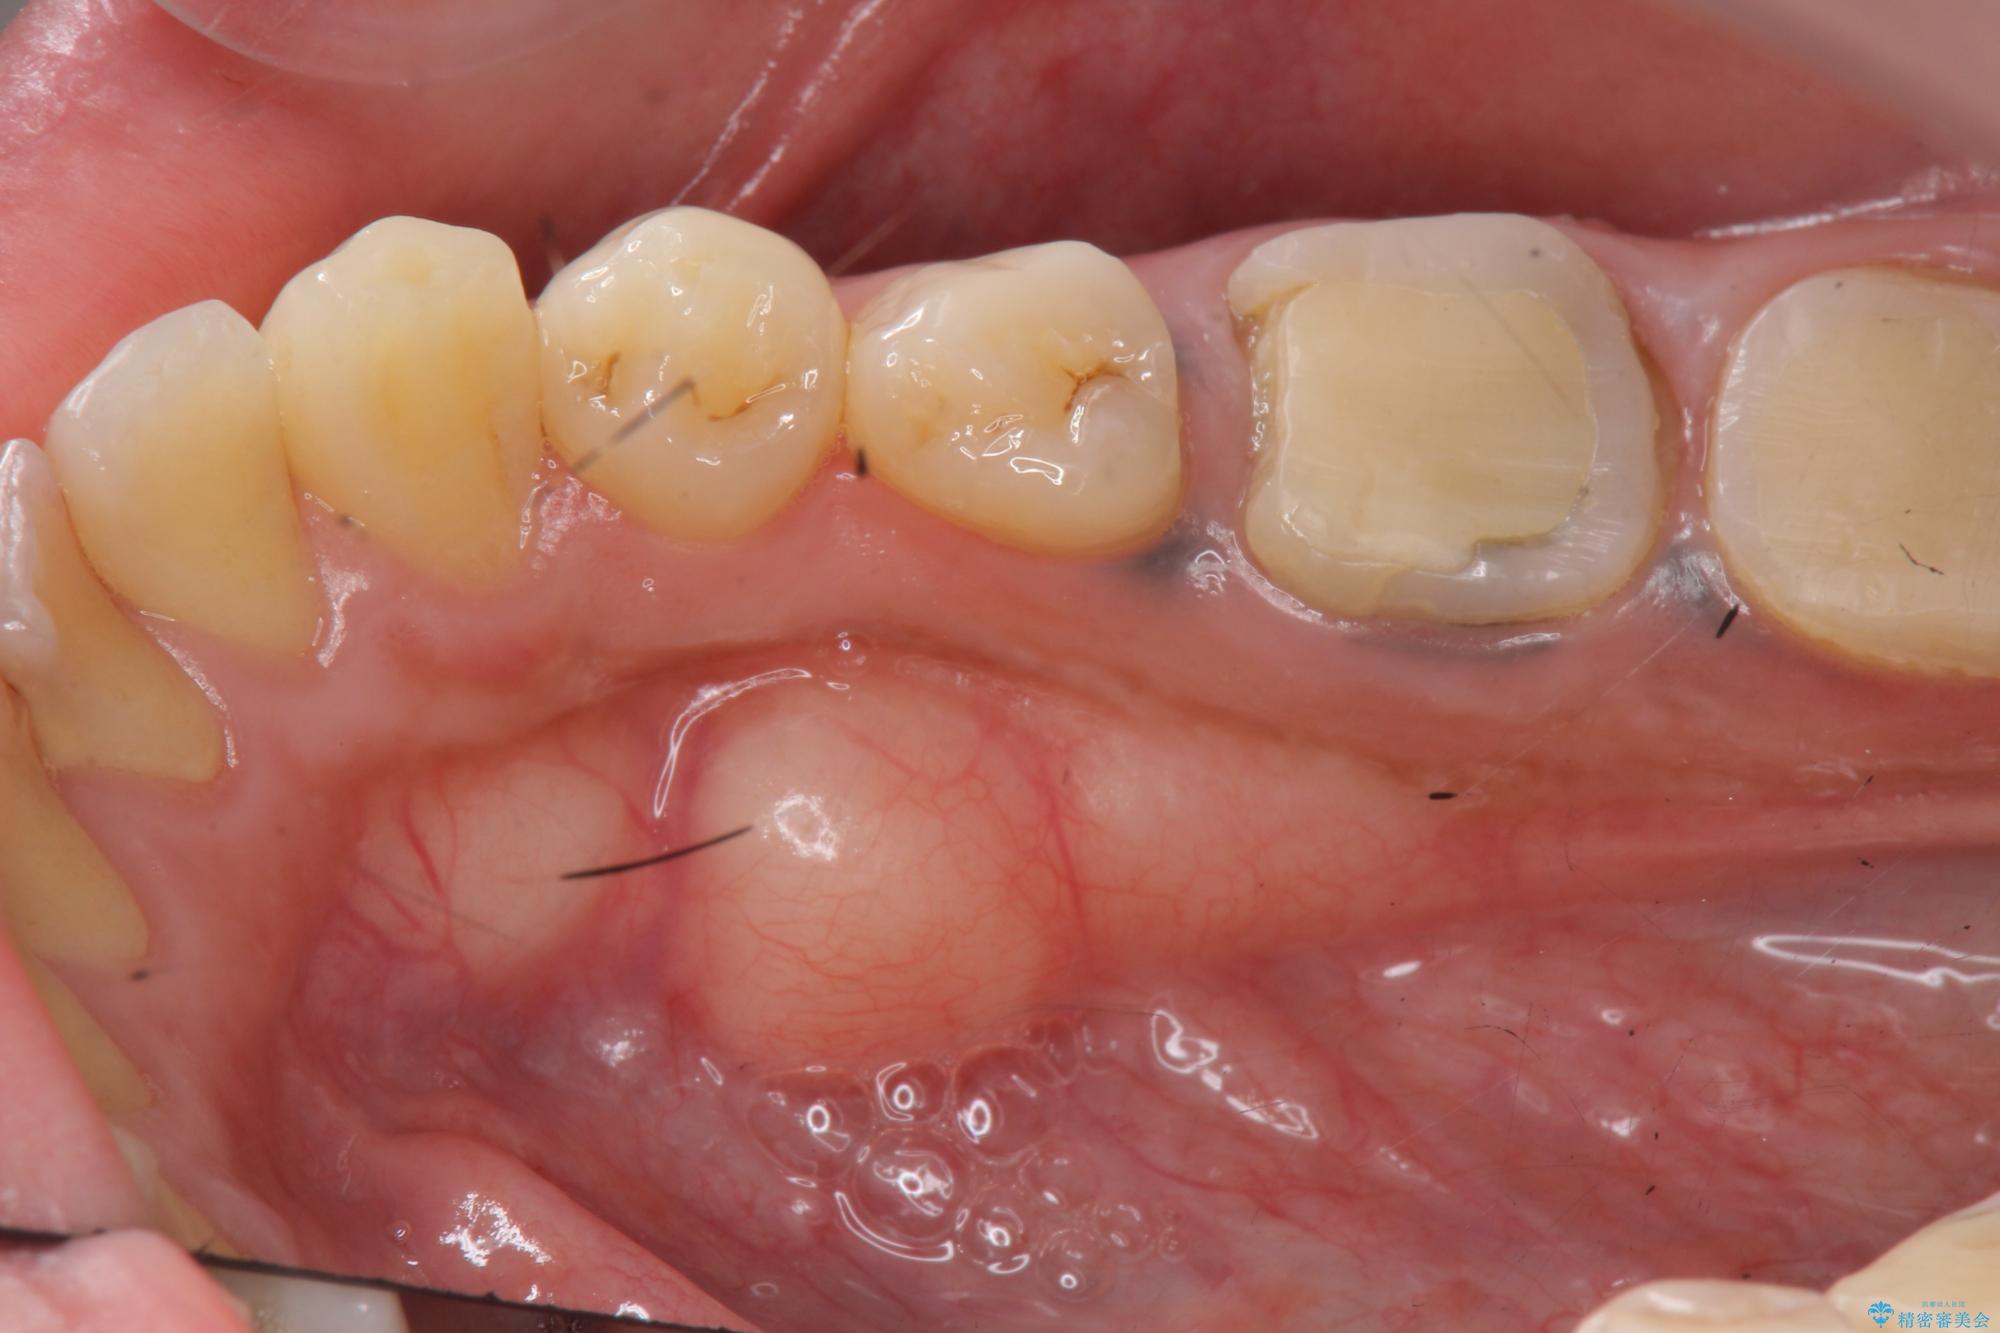

奥歯は既に根管治療が為されクラウンを装着する必要性がある状態ですが、歯の高さが低くクラウンの安定性・強度を担保するために歯周外科を行う治療計画としました。

歯周外科を行うことで、歯ぐきの位置を下げ歯の高さを作り出し安定したクラウンの装着が可能となります。また同時に舌の邪魔となっていた骨隆起の除去を行うこととしました。